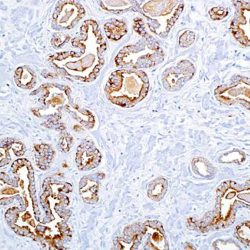

| Clone | Clone EP300 |

| REF | PSV-IHI0360 |

| Dilution | 1:50 |

| Staining | Cytoplasm |

| Control tissue | Tissue section from chromophobe carcinoma of the kidney |

| Isotype | IgG |

| Species of origin | Rabbit |

Intended use:

This antibody is intended for in vitro diagnostic (IVD) use. Primary Antibody is intended for professional laboratory use in formalin-fixed, paraffin-embedded (FFPE) tissue stained in manual qualitative immunohistochemistry (IHC) testing. A qualified pathologist must interpret the results using this product to aid diagnosis in conjunction with the patient’s relevant clinical history, other diagnostic tests, and proper controls.

Presentation:

Anti-human Parvalbumin rabbit monoclonal antibody purified from serum and prepared in 10mM PBS, pH 7.4, with 0.2% BSA and 0.09% sodium azide